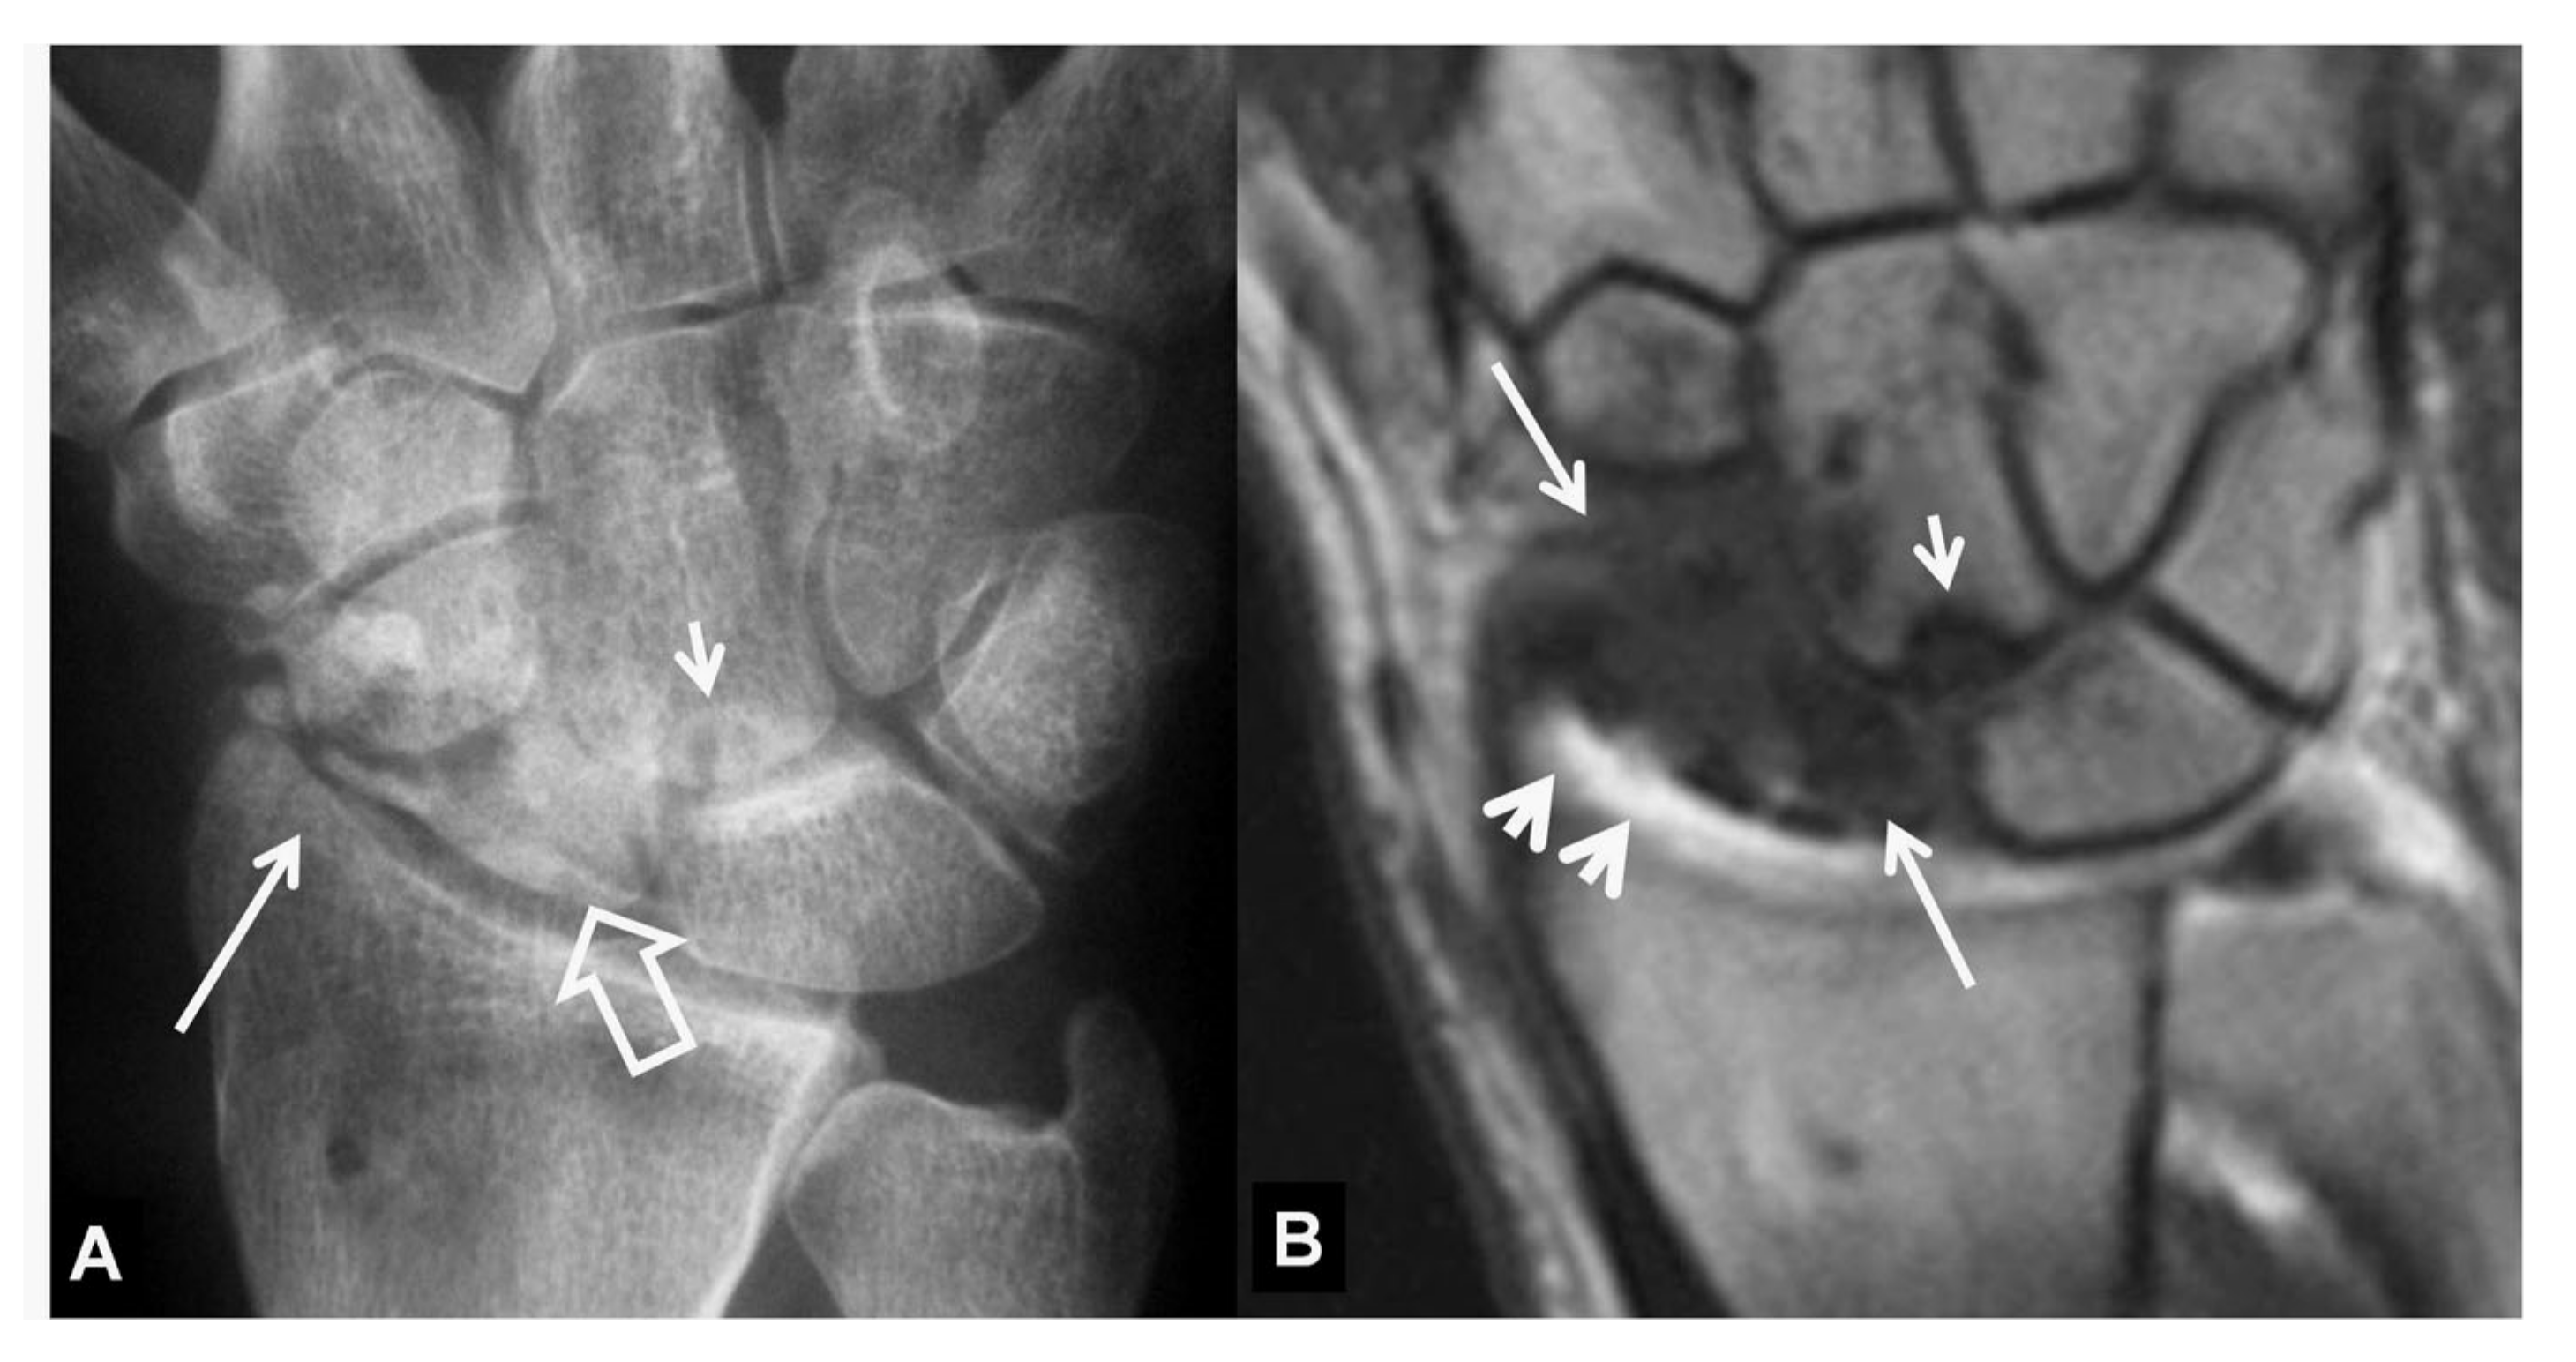

Figure 1.

A 23-year-old male patient with a history of a scaphoid fracture 1 year prior to current imaging. PA radiograph showing pseudarthrosis (arrow), proximal pole osteosclerosis in keeping with osteonecrosis (open arrow) and cyst formation on both sides of the previous fracture (short arrows). The radioscaphoid joint space is intact.

Figure 2.

A 34-year-old orthopedic surgeon, practicing in Boxing, presents with 3-month period of pain and limited range of motion.(A) PA radiograph showing the increased scapholutane distance suggesting scapholunate ligament rupture (open arrow). The finding is often called as the “Thery-Thomas” sing, after the famous actor teeth appearance. The “signet ring” sign is also evident due to the foreshortening of the scaphoid (arrows). (B) Coronal T2* MR image showing the absence of the low signal intensity membranous ligament (open arrow) in keeping with scapholunate ligament tear. The radioscaphoid joint space is intact.